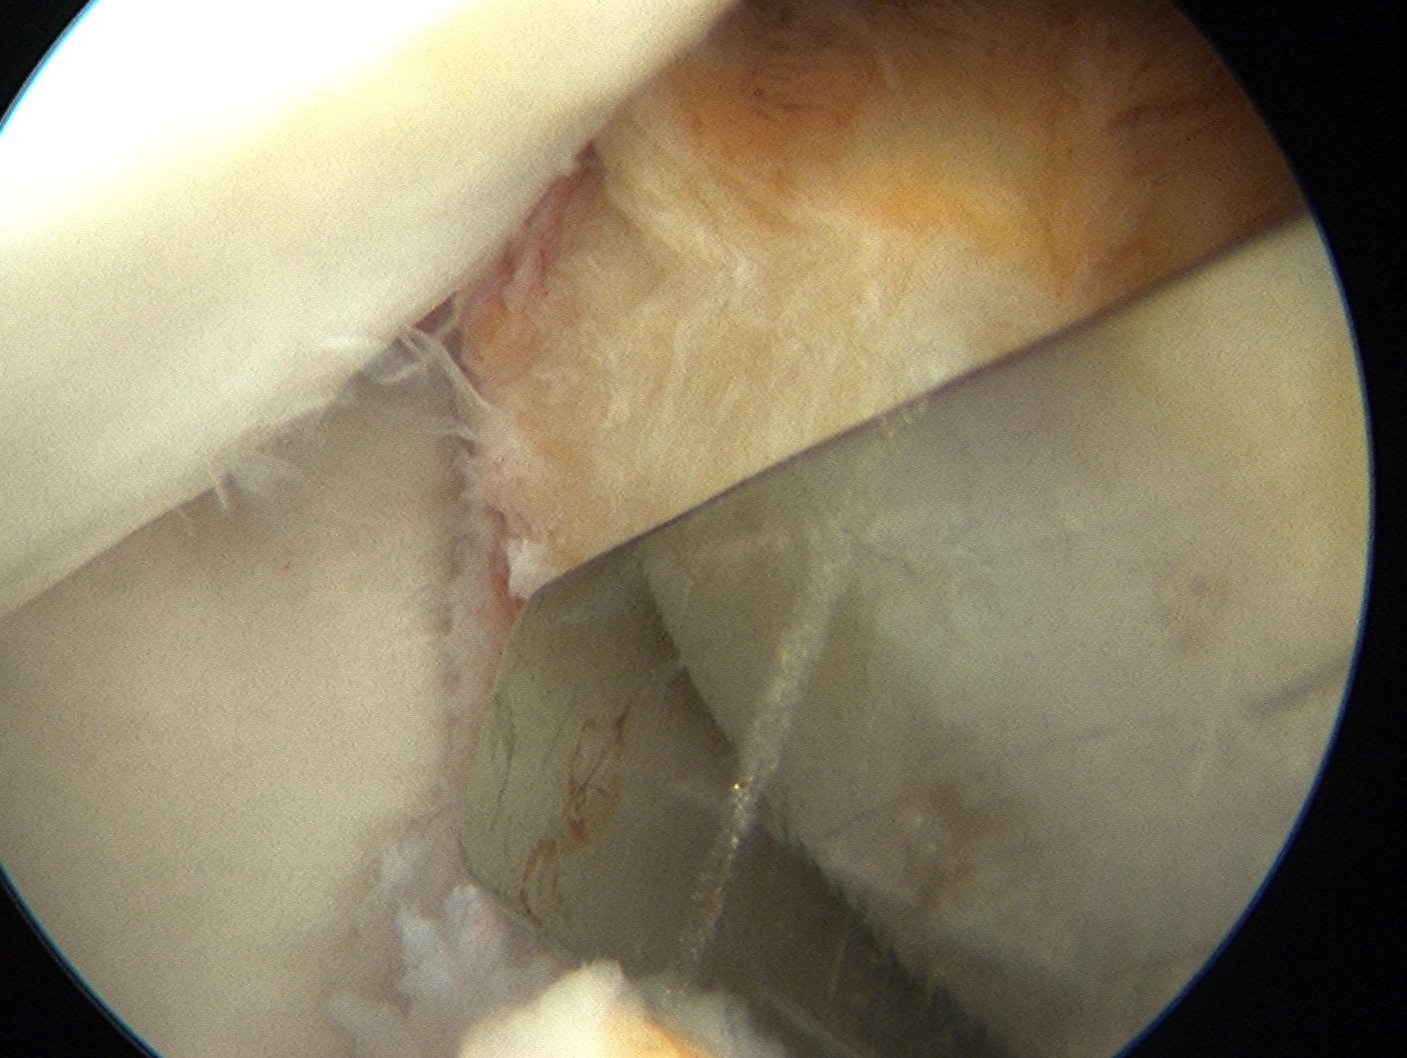

Insert anchors

Inferior anchor at 5.30 o'clock

- curved anchor guide / trans-subscapularis

- on rim of glenoid

Other anchors typically at 3 and 4 o'clock

Arthroscopy Bankart Anchor Drill GuideInferior Glenoid Anchor

Pass sutures and tie knots

Typically curved suture passers

Aim to tighten capsule medially and superiorly onto glenoid

Shoulder Bankart Repair Suture PasserShoulder Instability inferior Suture passage

Arthroscopy Anterior Bankart RepairShoulder Bankart RepairShoulder Scope Bankart Repair 2

Bankart repairBankart